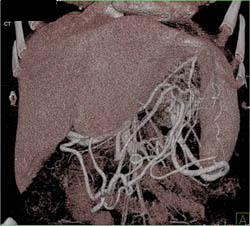

Intraductal Papillary Mucinous Neoplasm (IPMN)